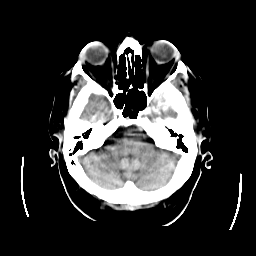

CT Study #2 -- Slice #6